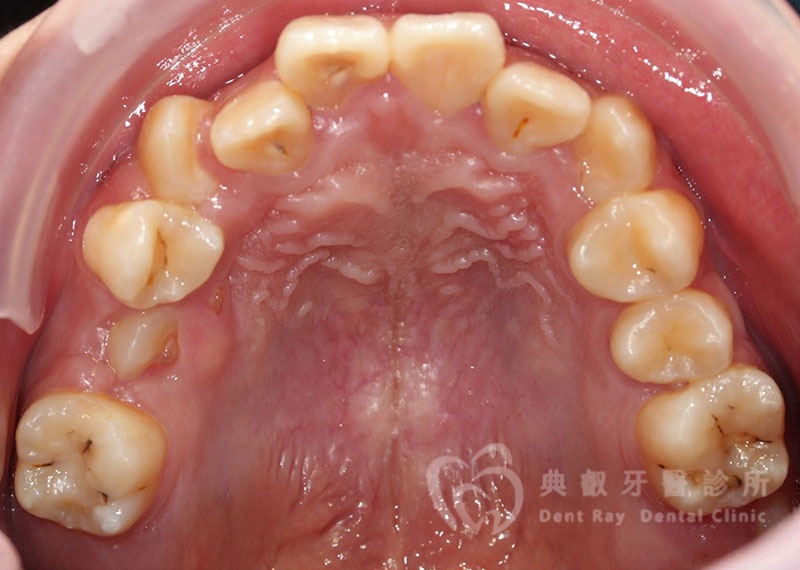

排列擁擠案例一

Before

After